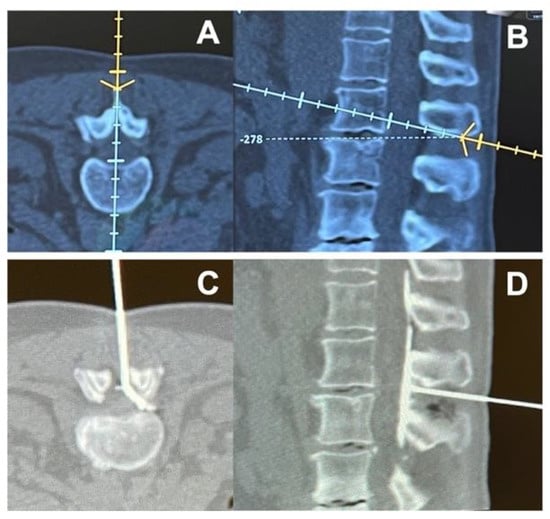

3.5. Image-Guided Epidural Injections